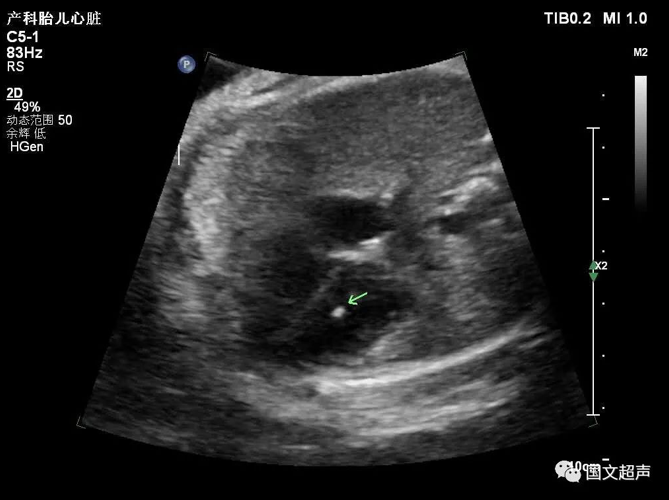

三.關(guān)于心室強(qiáng)回聲光點(diǎn)

胎兒心室內(nèi)強(qiáng)回聲光點(diǎn)不是一種心臟畸形,它只是一個(gè)聲像圖表現(xiàn),是胎兒染色體異常的一種潛在體現(xiàn),也被稱為超聲軟指標(biāo)(不是器質(zhì)的異常,其他的軟指標(biāo)還有NT增寬、腎盂分離、側(cè)腦室增寬、腸管回聲增強(qiáng)、四肢長(zhǎng)骨短、鼻骨短小等等)。

大部分強(qiáng)回聲光點(diǎn)隨孕周增加而縮小,回聲強(qiáng)度也逐漸減弱。到足月妊娠幾乎完全消失,少數(shù)則可一直存在,直至分娩,甚至產(chǎn)后超聲仍能觀察到。